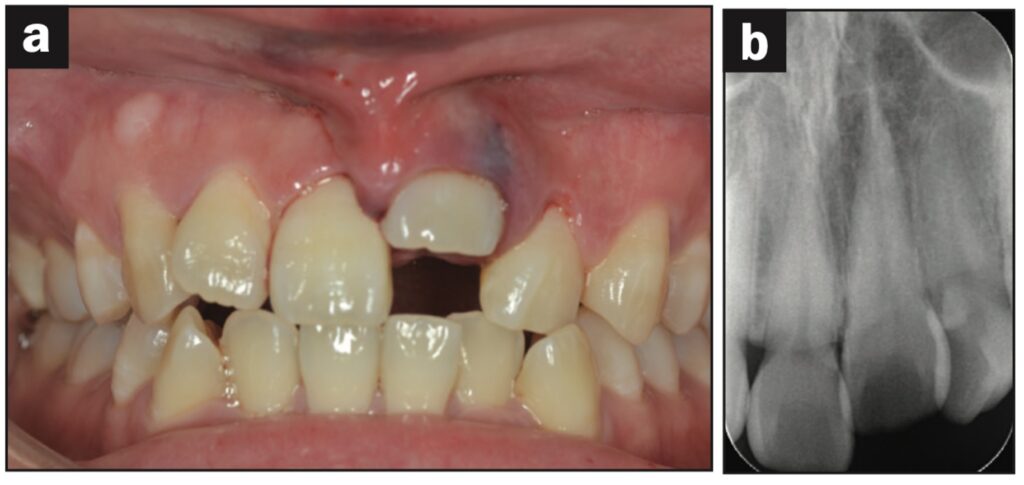

Bệnh nhân nữ 24 tuổi bị ngã khiến răng cửa giữa hàm trên bên trái bị lệch sang một bên. Sáng hôm sau, bệnh nhân đến phòng khám, được cố định bằng composite quang trùng hợp và lấy dấu.

Sáu tiếng sau, bệnh nhân quay lại và nhận hàm duy trì.

Bệnh nhân được hướng dẫn đeo hàm duy trì cả ngày trừ khi đánh răng. Các thử nghiệm độ sống tủy được thực hiện sau 1, 7, 14 và 21 ngày. Kiểm tra độ lung lay răng, gõ, sờ, thử tủy EPT và chụp X quang sau 28 ngày. Răng có độ lung lay +1 theo chiều ngoài trong và không có đáp ứng với thử nghiệm tủy EPT.

Ba tháng sau, răng đã được trám phục hồi và đáp ứng EPT (8/10). Tại thời điểm tái khám sau 4 tháng, răng đáp ứng với EPT (4/10). Sau 5 tháng, ghi nhận có lỗ dò. Răng không đáp ứng với EPT. Tổn thương quanh chóp được nhìn thấy trên X quang.

Răng được chẩn đoán là hoại tử tủy và điều trị tủy được thực hiện trong 2 lần hẹn. Một tháng sau (6 tháng sau khi chấn thương xảy ra), lỗ dò biến mất và chụp X quang cho thấy quá trình lành thương (hình 2).